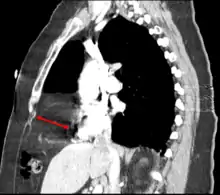

| Morgagni hernia seen on a chest radiograph. | |

Morgagni hernia

This rare anterior defect of the diaphragm is variably referred to as a Morgagni, retrosternal, or parasternal hernia. Accounting for approximately 2% of all CDH cases, it is characterized by herniation through the foramina of Morgagni which are located immediately adjacent and posterior to the xiphoid process of the sternum.[4]